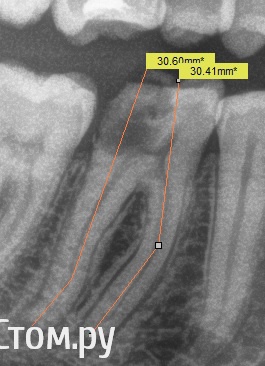

Shaid Опубликовано 28 января, 2014 Поделиться Опубликовано 28 января, 2014 Здравствуйте, уважаемые коллеги! Читаю форум с сентября 2011 года по настоящее время. За это время узнал больше, чем за всю учебу в ВУЗе. До сих пор не решался выложить что-либо на ваш суд. Но надо развиваться дальше и то подтолкнуло меня на создание данной темы, в которой я буду выкладывать удачные и не очень случаи из моей практики.Буду благодарен за любую критику. Итак, неделю назад пришла пациентка с желанием "подлечить все". После ОПТГ было решено начать с 4.6 зуба(кроме того, этот зуб начали лечить месяц назад, положив мышьяк, но не долечили). Глянув на снимок и ужаснувшись от длины корней этого зуба(30 мм по замерам оптг), я начал лечение, в первое посещение - ампутировал(да-да, он был живой несмотря на рентгенологич.картину) пульпу и создал доступ в каналы, сделал билд-ап из Vitremer. Во второе - первично прошел каналы и поставил Метапасту(не хватило времени). В третье, сколол клампом свой билд-ап мех, мед.обр-ка Протейперами до f2 насколько хватило длины инструмента, дальше - ручные. Мыл гипохлоритом, гуттой перемешивал. Обтурация - латералка .02 конусными. 10 Ссылка на комментарий